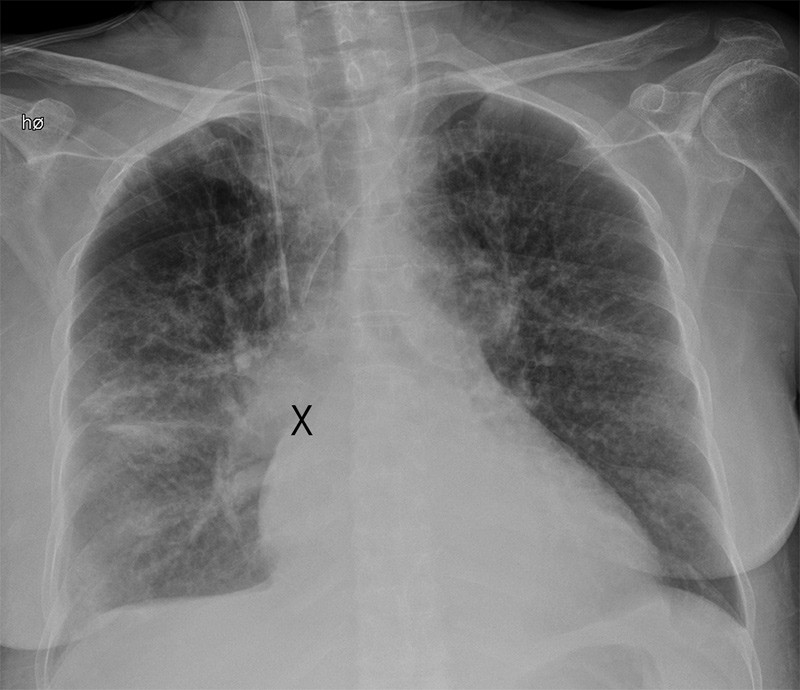

Ileus was initially suspected. Abdominal CT showed no free air or potential blockages, but raised suspicion of colitis in the right colic flexure. Areas of low attenuation in the lower pole of the spleen raised suspicion of splenic infarcts. Cefuroxime and metronidazole were administered on the basis of the unresolved abdominal condition and elevated infection parameters. Because of difficult peripheral intravenous access, a central venous catheter (CVC) was inserted via the right subclavian vein. Chest X-ray after admission showed that the catheter was correctly positioned with the tip deep in the superior vena cava. The patient deteriorated further, colonoscopy showed possible ischaemic colitis, and she was transferred six days later to the department of internal medicine. Since she was in a very poor state and clinically dehydrated with persistent electrolyte imbalance, she was placed in intensive care.

The possibility that the tip of the central venous catheter was inside an artery was ruled out by re-examination of the chest X-ray, and by the fact that electronic pressure measurements for the catheter lumen showed venous pressure levels.

The first catheter was positioned distally in the superior vena cava, such that powerful reflux from an atrial septal defect could conceivably produce a high ScvO2 value. However, the next two catheters were positioned more proximally in the superior vena cava, and it is difficult to explain high central venous saturation here in the same way (Figure 1).